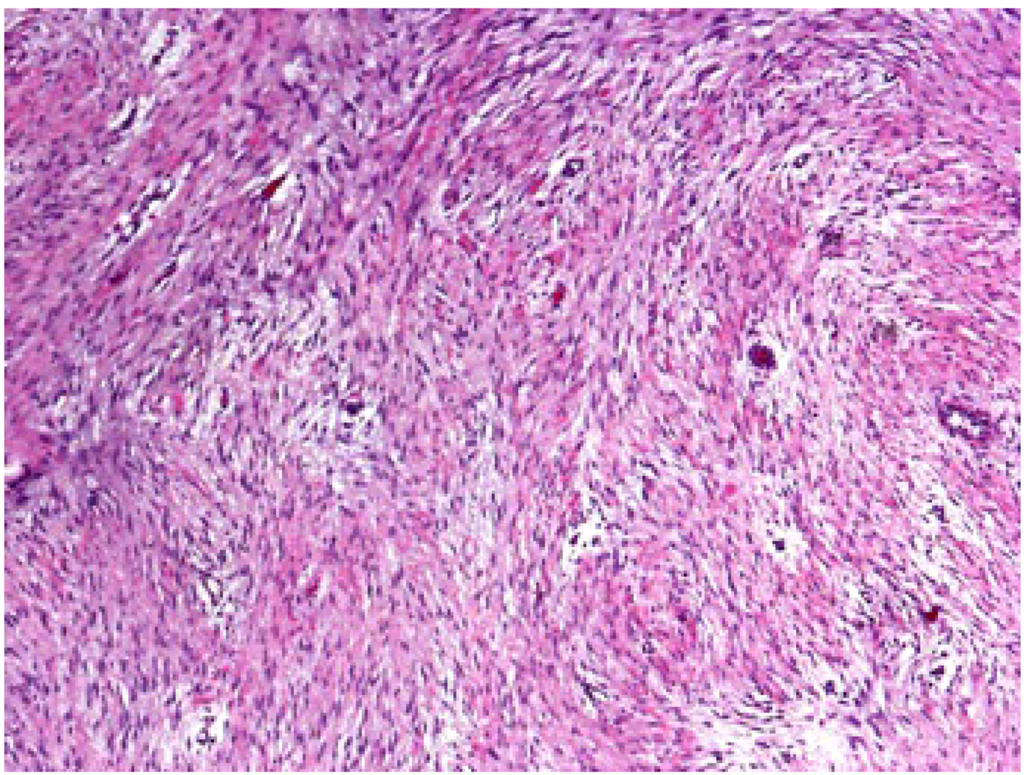

3. Clinical Presentation and Pathology